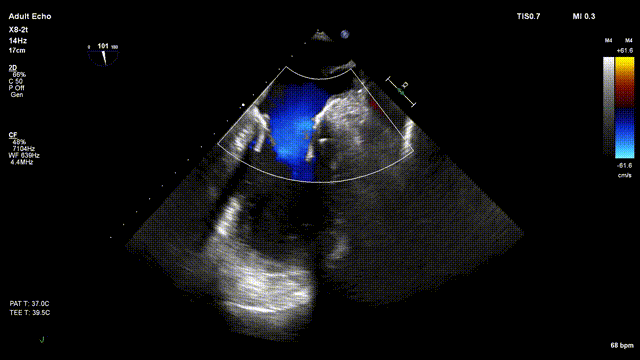

术前超声评估:

术前TTE超声提示二尖瓣大量反流